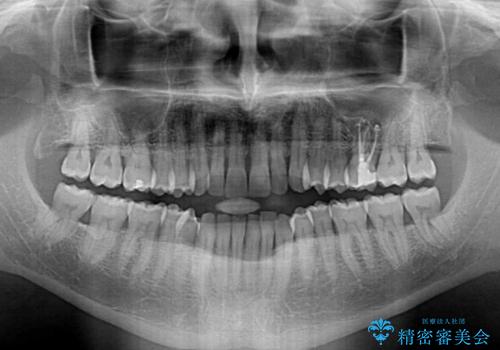

- 前歯でものを噛みきりたいとのことで来院された患者様です。

以前矯正治療を経験されたそうですが、舌の突出癖により上下前歯に隙間ができている様子でした。

舌の突出癖が改善されない限り、非接触改善は見込めないため、トレーニングを徹底するように指示しました。